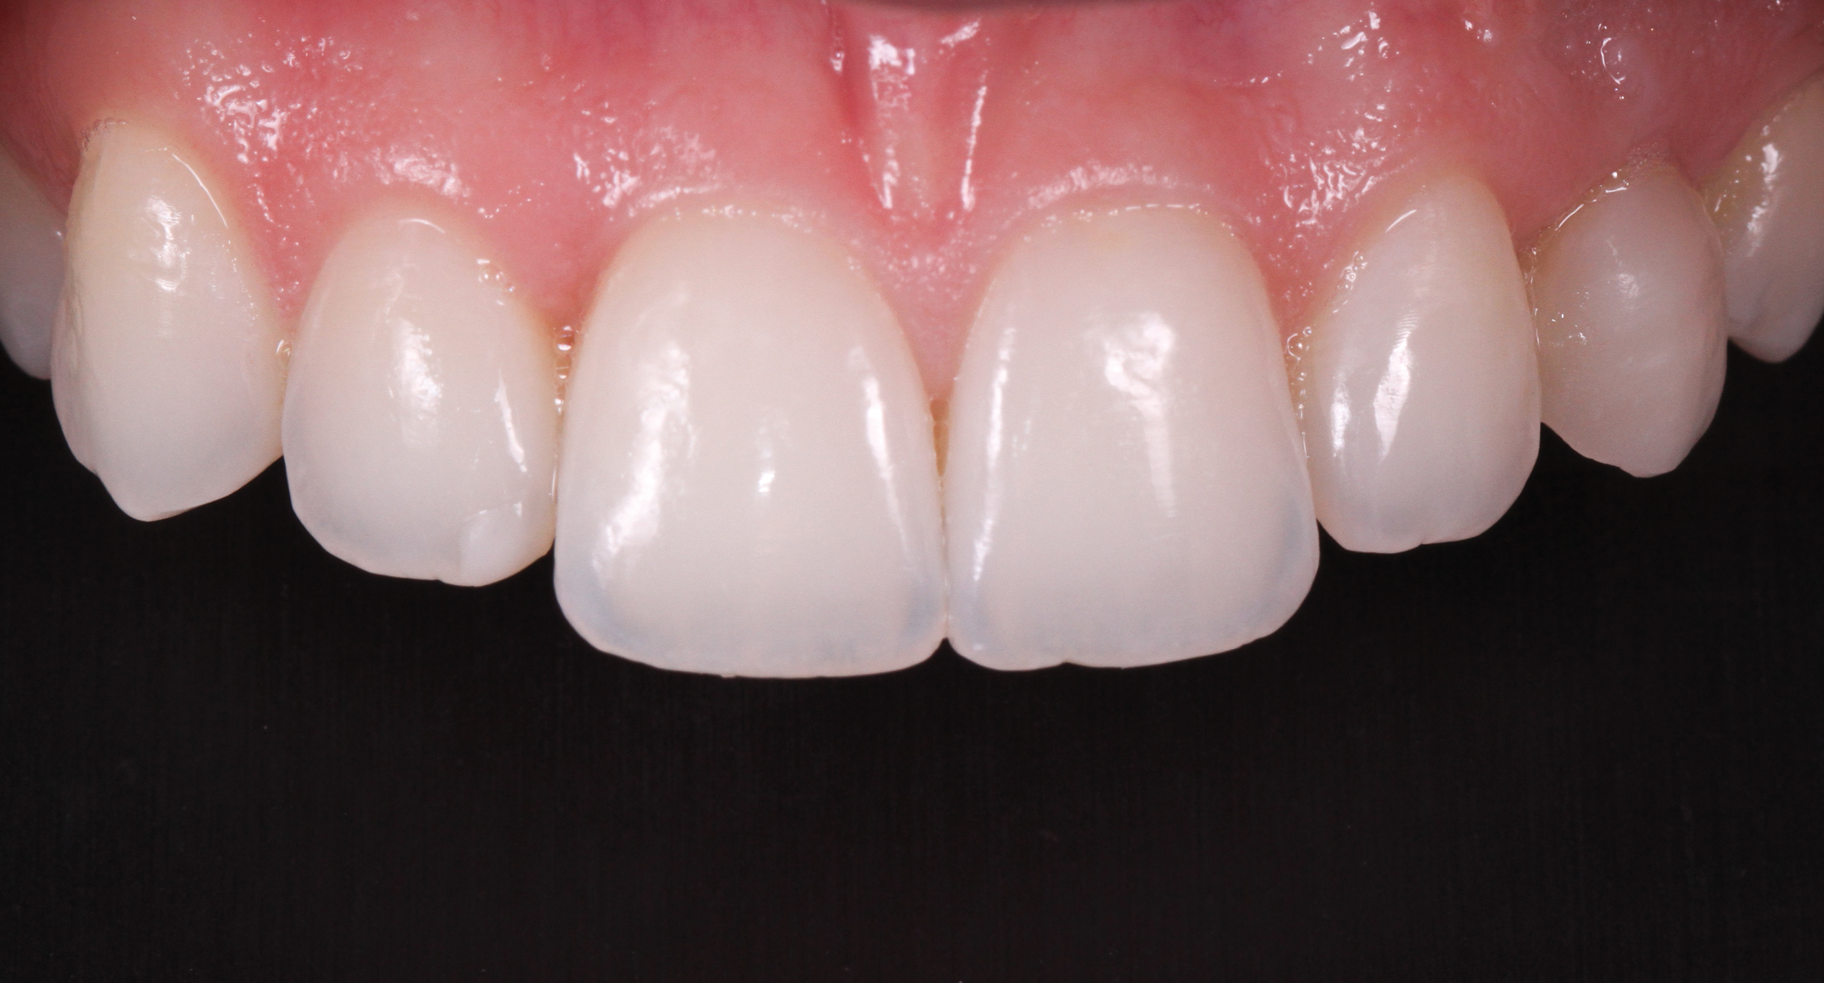

(33.) Retracted view with the teeth apart and close-up view of the definitive screw-retained zirconia restoration in position (Definitive restoration fabricated by Sam Alawie and Beverly Hills Dental Lab).

Figure 33

(34.) Retracted view with the teeth apart and close-up view of the definitive screw-retained zirconia restoration in position (Definitive restoration fabricated by Sam Alawie and Beverly Hills Dental Lab).

Figure 34